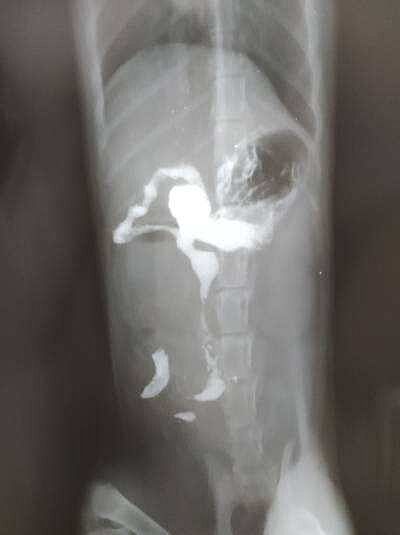

только пришли. сделали рентген, на снимке непроходимость в верхнем отделе кишечника, на выходе из желудка.

иначе вечером прооперируют после контрольного снимка.

влили 25 кубиков контраста, он имеет хорошие обволакивающие свойства, а значит есть шанс. что до вечера этот злосчастный комок может сдвинуться по кишечнику.

очень похоже. что это кляп из шерсти. как я и предполагала

вот что ответил один из хирург-эндоскопист

’Добрый день, судя из рентгеновских снимков, непроходимость у животного наблюдается в тонком отделе кишечника. В таком случае эндоскопическое вмешательство не показано, оно используется только для извлечения инородных тел полости желудка’

вот наш рентген. вдруг кто-то разбирается? нам через два чаа на повторный рентген и тогда уже будет совсем мало времени для маневра. Если этот затор не сдвинулся от контраста, скорей всего сразу под скальпель